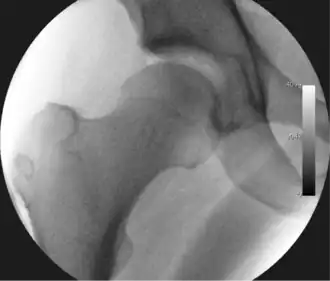

Figure 4. A needle is passed into the joint, breaking the 'suction seal', and allowing further distraction of the hip joint with minimal extra traction

The next step is to insert a fine needle under x-ray guidance into the hip joint. This breaks the 'suction seal' of the joint and allows further distraction if necessary (see fig 4). The surgeon wishes to see the ball move out the socket by approximately 1 cm, so that access to the hip joint can be achieved with minimal risk of damage to the joint surfaces. Most surgeons will inject fluid into the joint at this stage, again to ensure that there is enough space between the ball and socket for safe instrument access. This needle is then removed. The next step is placement of the 'portals', or the small holes made to pass instruments into the joint. This is achieved by again passing a fresh hollow needle into the joint under x-ray control, usually in a slightly different position. The reason for this is so the surgeon can ensure that the needle, and subsequent cannulae do not penetrate and damage the acetabular labrum or cartilage joint surfaces (see fig. 5). Again, surgeons will have their own preferences as to their preferred placement. Through this hollow needle, a long thin flexible guide wire is passed into the joint, and the needle is removed over it, leaving the guide wire in situ. A small cut in the skin is made around the wire, to allow for larger cannulae to be placed over the wire through the portal. The wire therefore guides the larger cannulae into the joint. The most common external diameters of cannulae used are between 4.5 and 5.5 mm. Once the surgeon is satisfied that the cannula is in the correct position, by a combination of feel and x-ray guidance, the guide wire can be withdrawn. Once the first portal is correctly placed, any further portals may be created once the camera is in position, to ensure that they are placed with minimal risk to the joint surfaces. This process can be repeated to gain as many points of entry to the hip joint as the surgeon requires, normally between two and four. Certain of these entry points will be used for the viewing arthroscope and others for operating instruments.